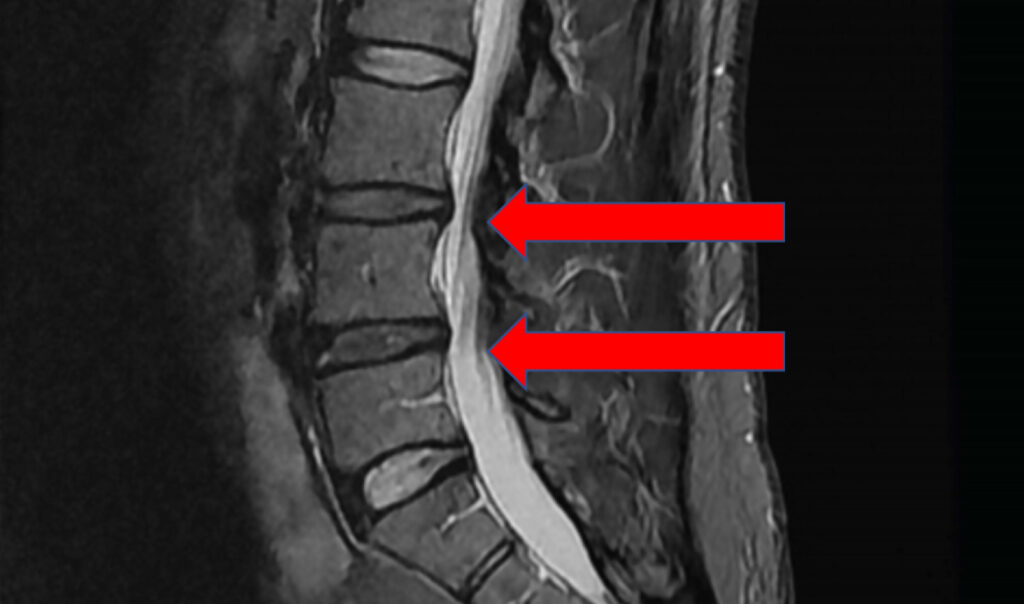

An MRI revealed that Jeff had suffered damage to several spinal disks in his middle and lower back. This further resulted in several pinched spinal nerves (radiculopathy).

At this point, Jeff was in severe distress. His pain was ongoing and frequently severe (7 to 9 out of 10) when not being partially controlled by medication. He was also dealing with muscle spasms, dizziness, and tingling that radiated into his arms and legs. The pain limited his range of motion, making it difficult to work out or accomplish daily tasks. It was also making it difficult for him to sleep.